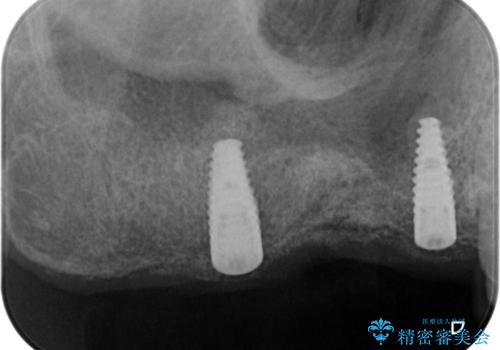

インプラント埋入時に骨の造成を、2次手術時に歯肉の凹みを整え厚みを一定にするような治療を進めていきます。

- 106.7万円 (インプラント×2 アバットメント×2 ジルコニアクラウン×3 骨造成 )費用は治療当時の料金となります